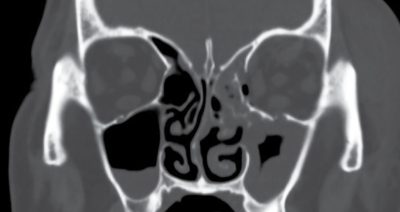

A képanyagot áttekintve a bal oldali orbita mediális és laterális csontos falának diszlokációjával járó törése látható, a külső szemizmok megkíméltségével, az ethmoid sejtek kitöltöttségével és a sinus maxillaris körkörös nyálkahártya megvastagodásával (2. ábra).